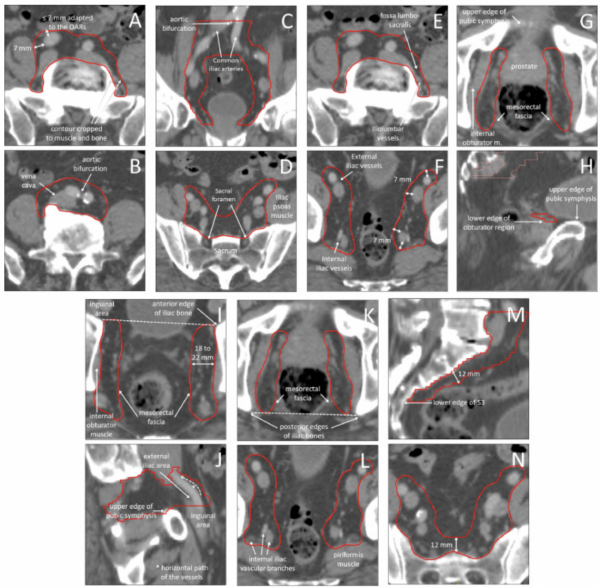

22.09.2023 Konturowanie węzłów chłonnych w raku prostaty – wytyczne Francophone Group of Urological Radiation Therapy.